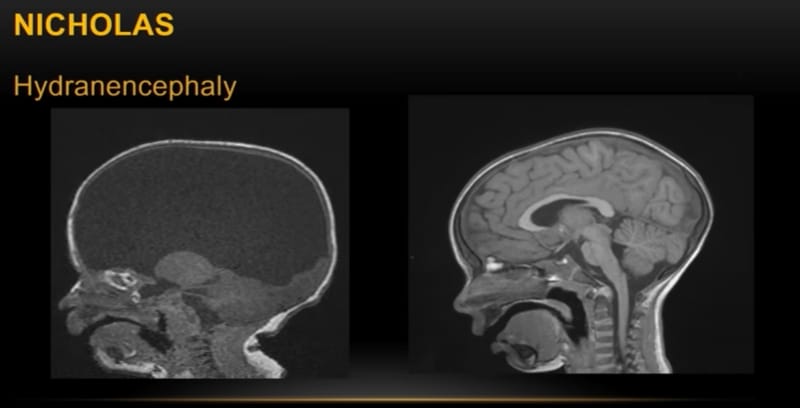

Nicholas is a little boy who's quite handicapped. He has cerebral palsy and he's missing both hemispheres of his brain. The only part of his brain he has is his brain stem. He is handicapped. He can't speak. He can't walk. But he's fully conscious. He's kind of funny. He laughs. He cries. He's emotionally a normal person even though he is handicapped, even though he's missing his entire brain hemispheres.